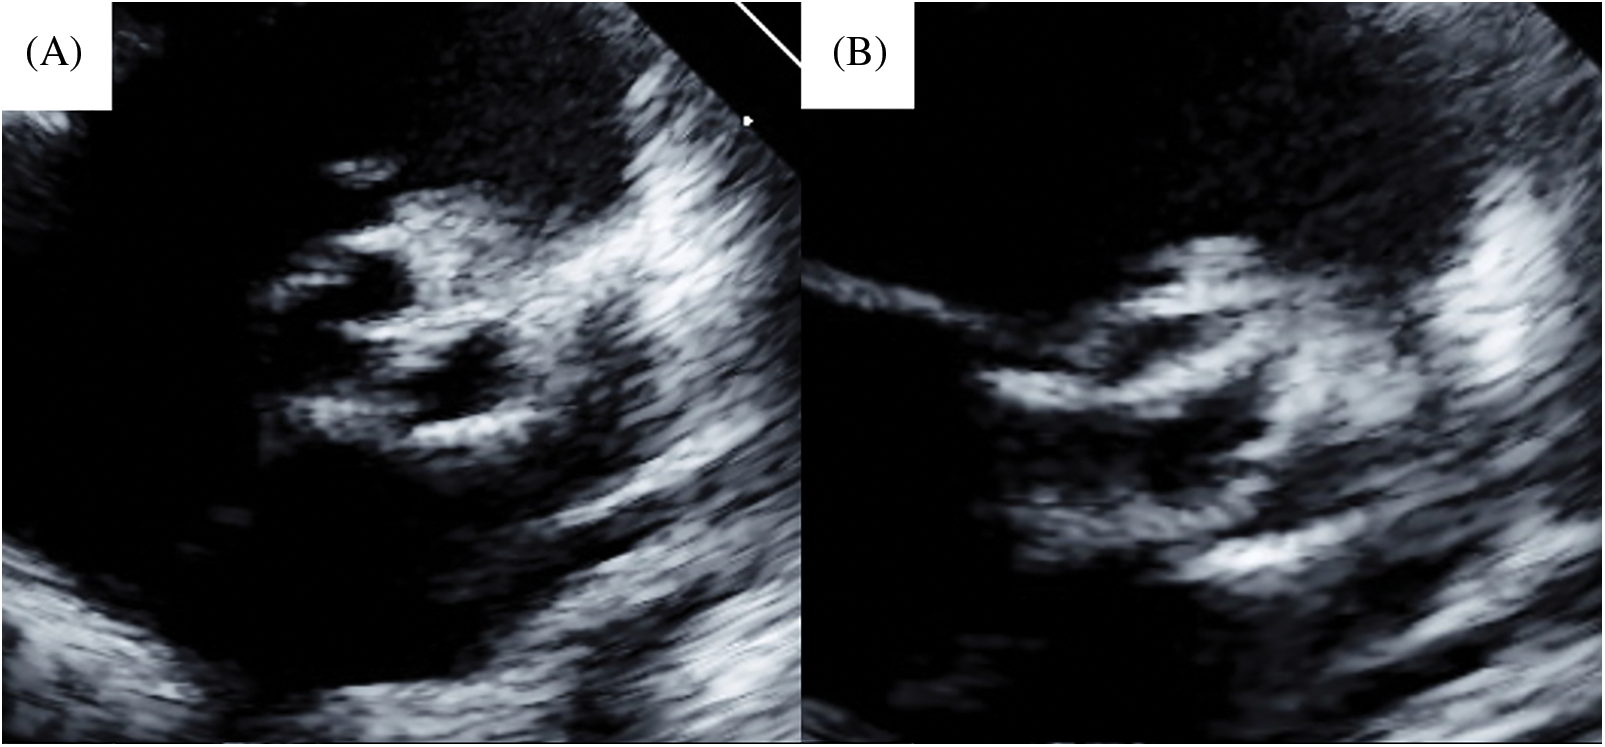

Simultaneously, the left and right cusps were divided at the anterior commissure. Both cusps were sliced to improve mobilization. We performed bicuspidization by commissuroplasty [3] using glutaraldehyde-treated (3 min) autologous pericardium (Figs. 2 and 3). The commissure was made along the longitudinal aortotomy site. Concomitantly, we performed coronary ostium augmentation of the left coronary artery. The cardiopulmonary bypass and cardiac arrest times were 157 and 87 min, respectively. Postoperatively, no AR was observed, and the peak velocity through the aortic valve was 1.9 m/s (Figs. 4A and 4B). A follow-up at 8 years postoperatively (Figs. 4C and 4D) revealed mild AR and a peak velocity of 3.9 m/s with mean pressure gradient of 35.9 mmHg. In addition, the end-diastolic posterior wall thickness was 6.49 mm (113% of normal, Z score = 1.7), which suggested left ventricular hypertrophy. He had no signs of heart failure. His aortic annular diameter increased along the normal annular diameter (Fig. 5), with a recent aortic annular diameter of 15.9 mm (113% of normal, Z score = 2.1).

BVP is usually selected for neonates because of the difficulty of valve repair and intolerance of surgery. Even at our institute, the first choice for cAS with unicuspid aortic valve is BVP. However, surgery must be performed when moderate or severe AR occurs concurrently or when BVP is ineffective, as in case 1. Moreover, when intervention for the aortic valve in neonates can be avoided, as in case 2, aortic valve repair is the first choice because of certain release of stenosis and control of regurgitation. Clear surgical space is required for fine valve repair in such aortic valve repair during neonatal or early infancy. We have previously reported an open-sleeve technique to solve this problem [1,2]. In this technique, the longitudinal incision of the aorta can be controlled by Valsalva, ventriculoaortic junction, or the ventricular muscle if required. In the two cases reported here, the aortic valve was unicuspid, and commissural height was low; therefore, achieving satisfactory valve function with commissurotomy only was challenging. Thus, we performed bicuspidization by commissuroplasty. The annular diameter was small because of their age. Therefore, we concomitantly used the open-sleeve technique for a clear and wide surgical space. Commissuroplasty can be performed at the site of longitudinal incision in a series when this incision is made at the opposite side of the well-developed commissure.